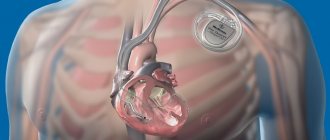

A pacemaker (pacemaker) is a small device, weighing approximately 30-50 grams, capable of creating electrical impulses that regulate heart rate. It is installed when it is necessary to maintain rhythm in patients with bradycardia or atrioventricular block, when the heart works intermittently.

A pacemaker, as a rule, consists of two parts: a metal case containing a battery designed for 7-10 years of operation and a microprocessor unit that provides heart rate setting and other parameters; the second part is the electrodes, through which electrical impulses propagate from the pacemaker into the chambers of the heart. Pacemakers are the best treatment for bradyarrhythmias. The first pacemaker was implanted in 1958.

A pacemaker essentially consists of three parts: an electrical pulse generator, a battery, and a series of wires with electrodes on their tips. The battery powers the generator, and both are surrounded by a thin metal casing that is connected to the heart by wires.

Modern lithium-ion batteries have not only extended the service life of the pacemaker to approximately 15 years, but have also made it possible to significantly reduce its dimensions. Now the generator and battery are placed in a titanium box measuring 5x4.5x1 cm, weighing only 20 grams. Wires extend from this box, which through a vein or artery reach the desired area of ​​the heart to stimulate contractions. There can be from one to three such wires; the type of pacemaker depends on their number: one-, two-, or three-chamber.

A single-chamber pacemaker has one such wire that connects it to one chamber of the heart: this can be the right atrium or the right ventricle. A two-chamber pacemaker is connected to two cavities of the heart, and a three-chamber pacemaker, accordingly, has three wires. Such a pacemaker can stimulate both the right atrium and both ventricular cavities. The pacemaker is selected and programmed individually for each patient, taking into account the rhythm of his heart.

A pacemaker is implanted into a person's body (usually under the subcutaneous fat of the chest) and connected to the heart muscle using electrodes. A pacemaker acts on the heart muscle in the absence of a natural heart rhythm, that is, it produces an electrical impulse. As a result of this impulse, the heart muscle contracts. Nowadays, pacemaker implantation is considered a simple operation that is performed under local anesthesia. But once upon a time, this was a serious, life-threatening surgical intervention.